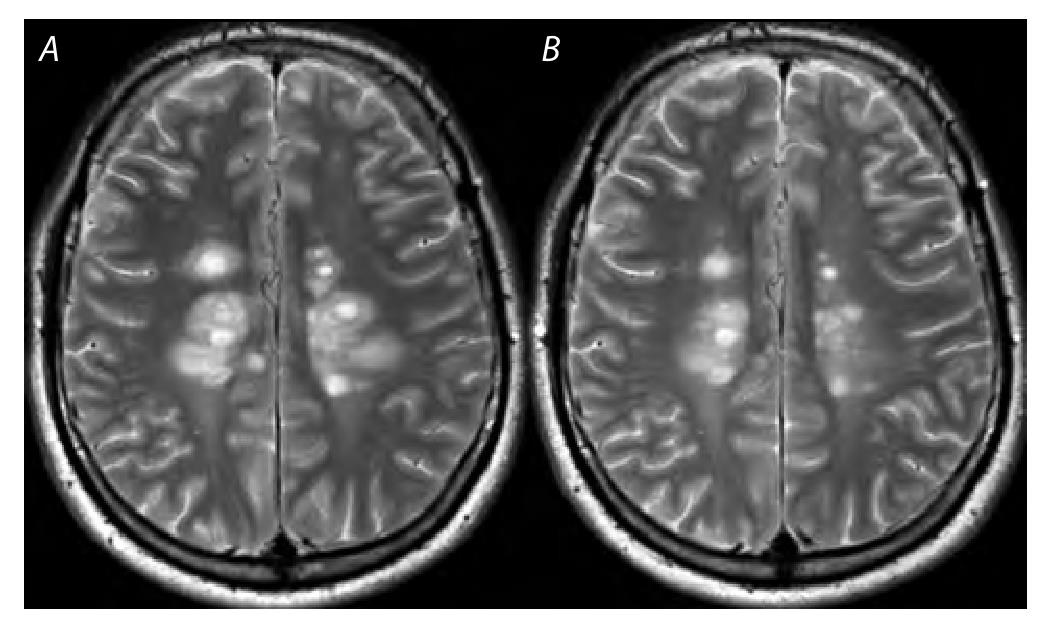

Рис. 4. Пациент С.

A — до терапии ВГКС: T2WI, множественные очаги демиелинизирующей природы с выраженным перифокальным отёком в белом веществе лобных и теменных долей; B — после терапии ВГКС: выраженный регресс нескольких ранее обнаруженных патологических очагов.

Fig. 4. Patient S.

A — before the IVGC treatment: T2WI, multiple peripherally edematic demyelination foci in the frontal and parietal white matter; B — after the IVGC treatment: significant regression in several previously detected lesions.

Следует отметить, что у 1 пациента из группы с метаболическим ответом на ВГКС на T2-МРТ-изображениях при МРС наблюдалось значительное уменьшение объёма нескольких обнаруженных до терапии очагов и умеренное восстановление (снижение) интенсивности пика холина (рис. 4). Большинство описанных случаев метаболических ответов представлены у пациентов с РРС с клинически подтверждённым обострением, но отсутствием контраст-позитивных T1-очагов на МРТ.